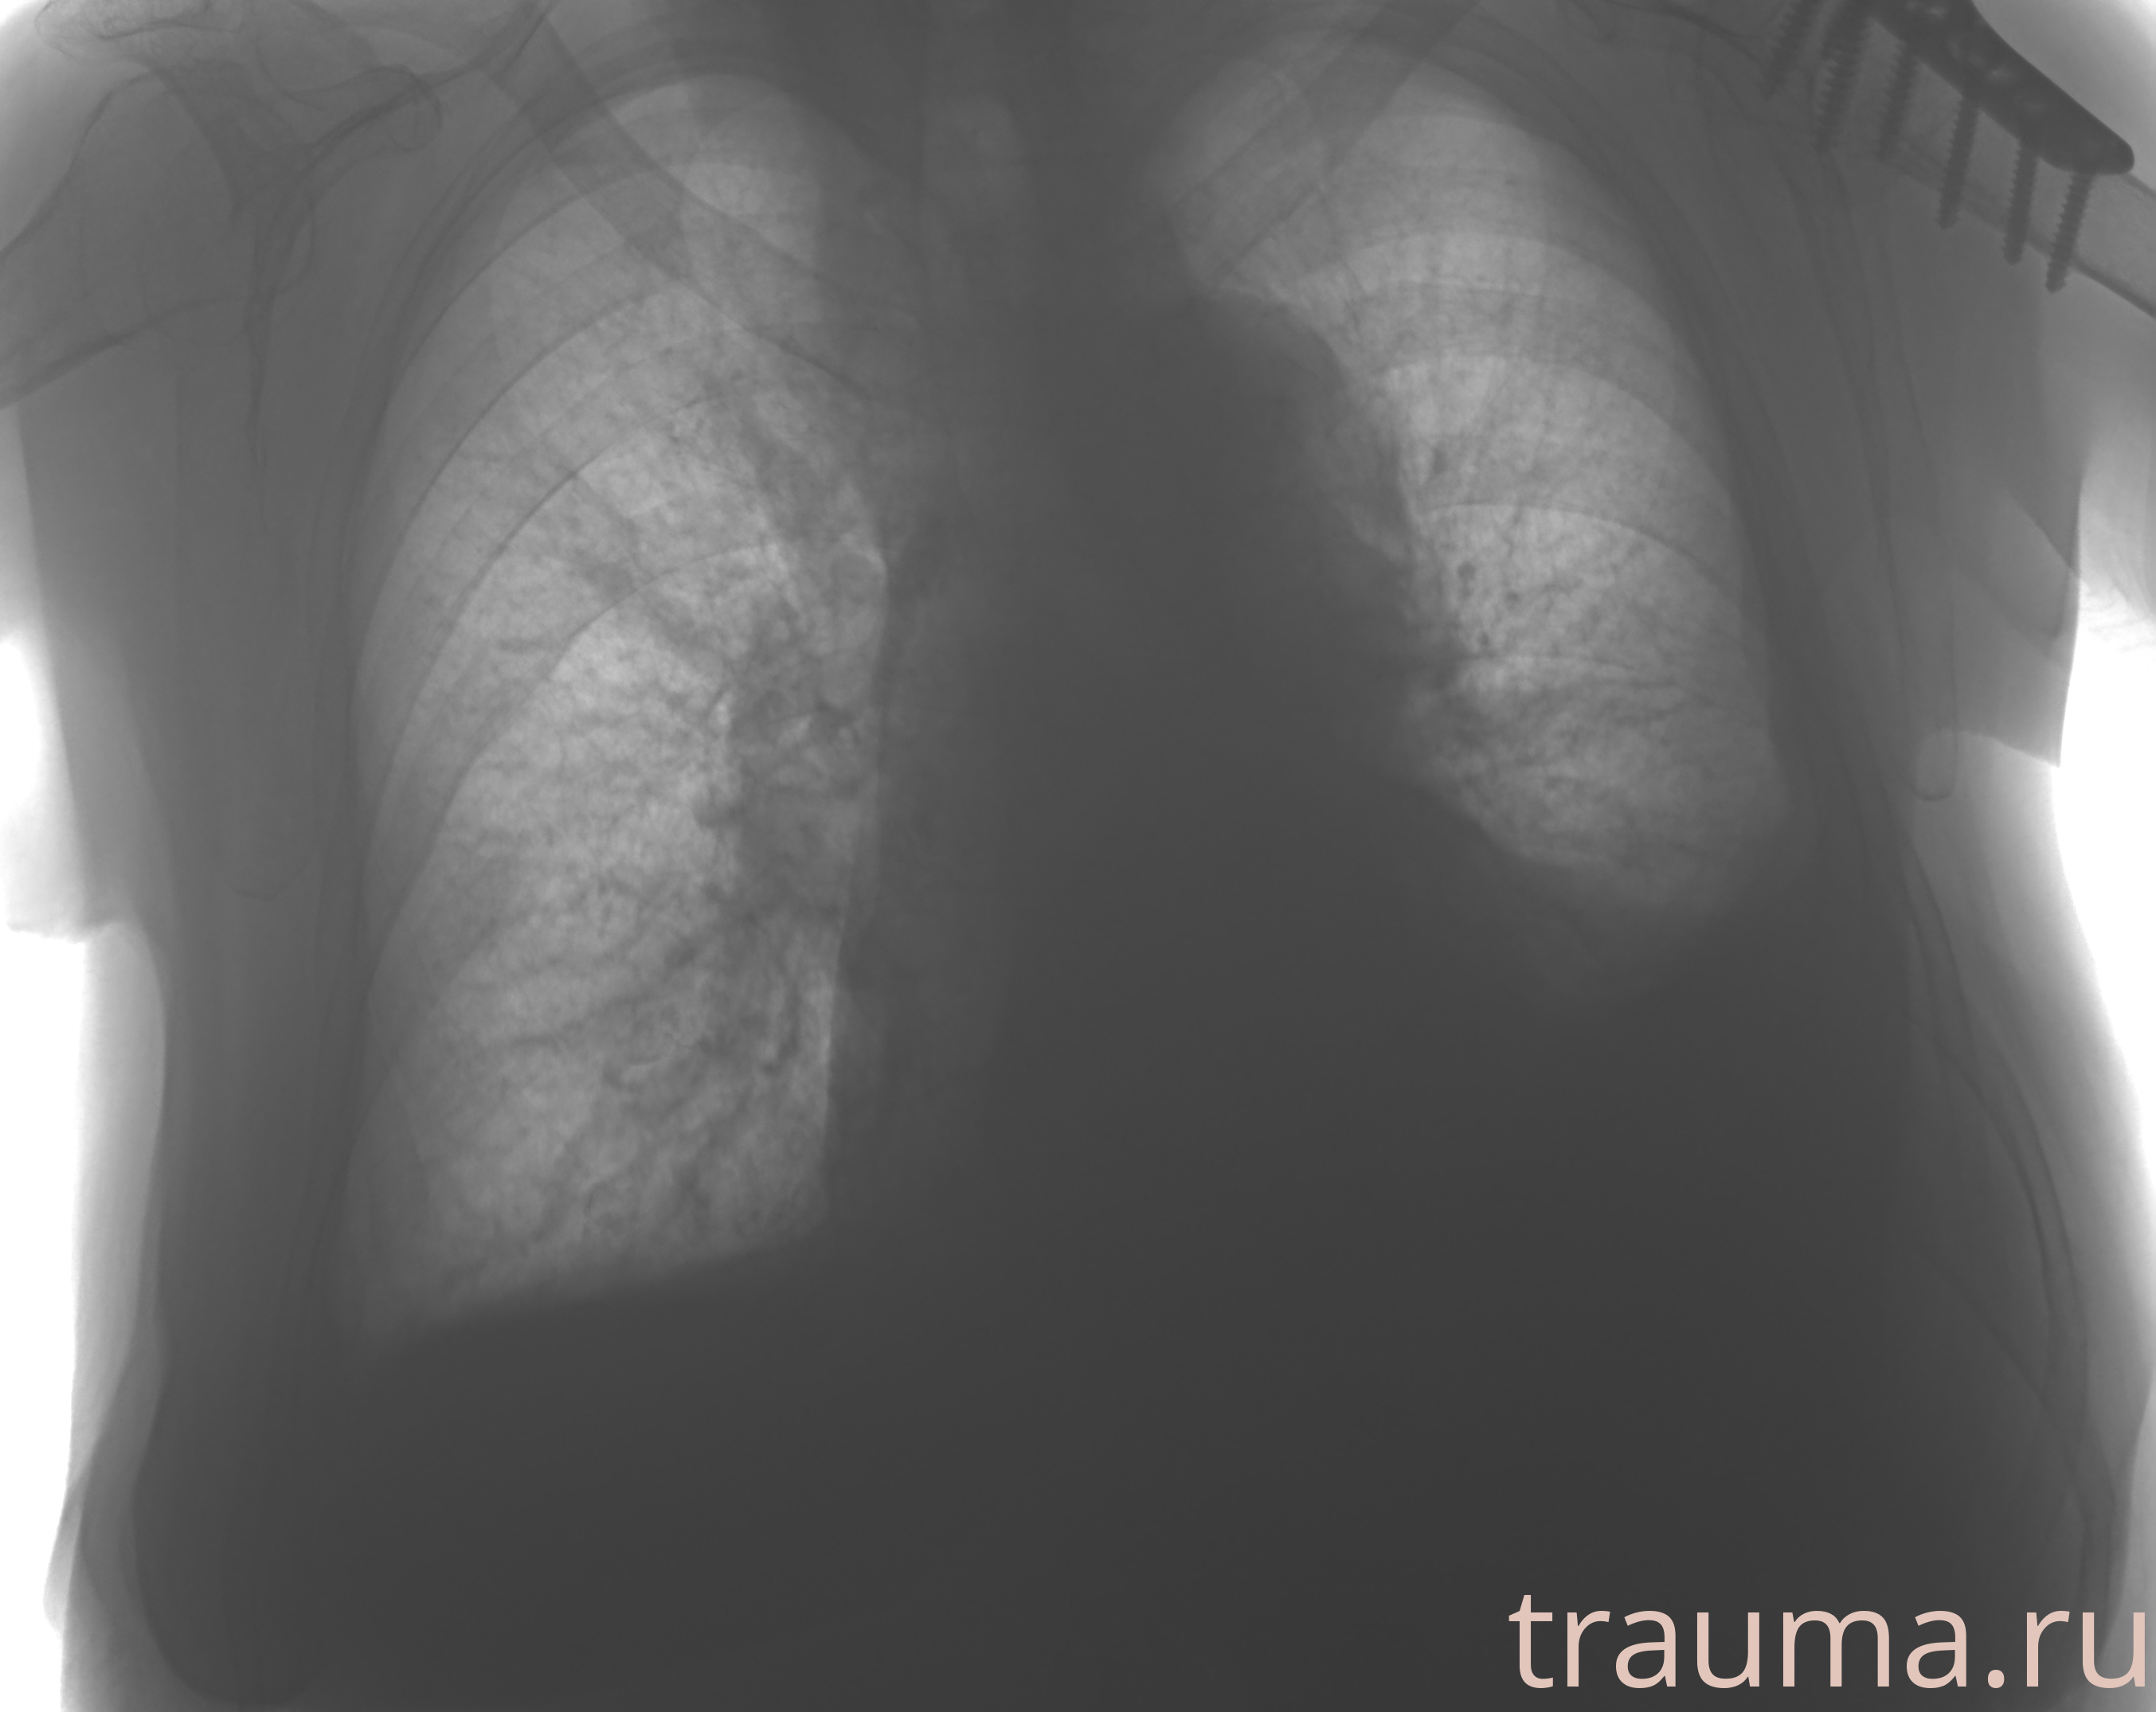

Рентген на дому: по вашему адресу приезжает врач-рентгенолог, травматолог-ортопед с мобильным рентгеновским аппаратом, проводит диагностику травмы или заболевания, делает необходимые рентгенограммы, дает рекомендации по дальнейшему лечению. Получить качественные снимки в домашних условиях возможно благодаря уникальной методике, разработанной МосРентген Центром для института  Склифосовского

при переломе шейки бедра и пневмонии от компании МосРентген Центр - партнера Института имени Склифосовского